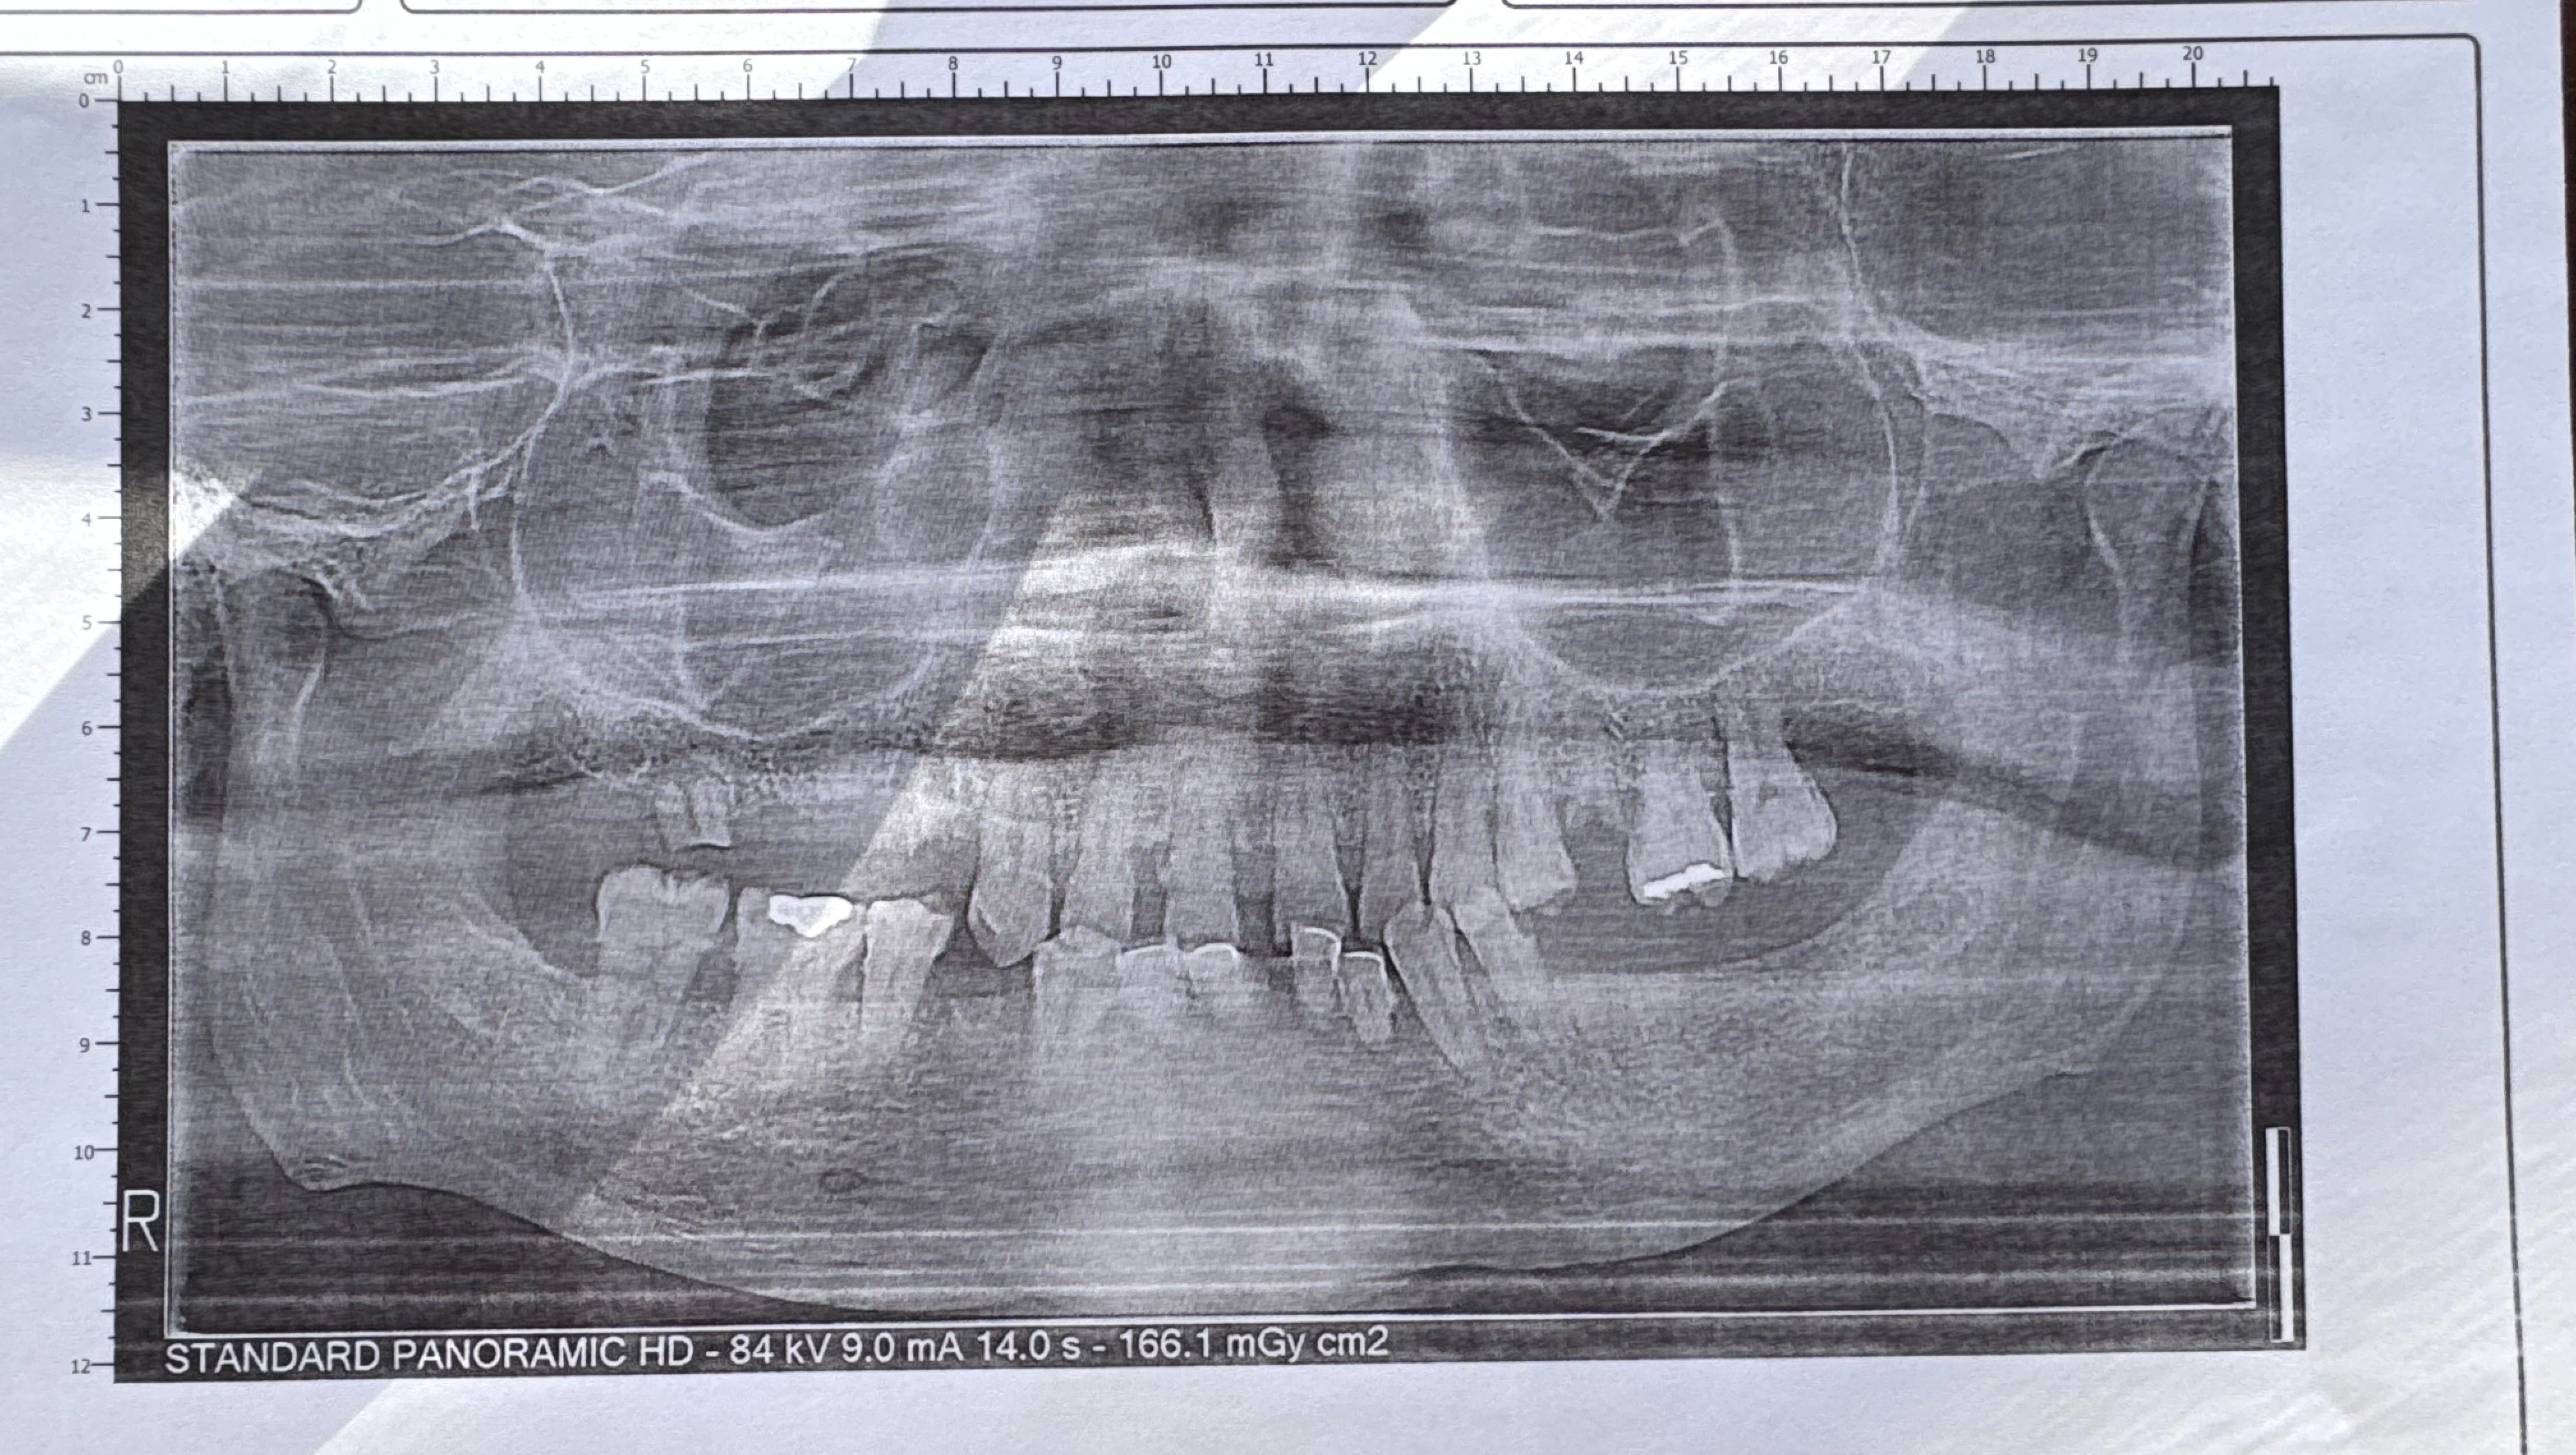

On a recent episode. I interviewed Shannon. He has overcome so many obstacles in life including addiction, homelessness, and so much more. For 24 years of his life he lived on the streets of Atlanta and SURVIVED. Due to years of homelessness, lack of dental hygiene, and addiction Shannon needs to have dental surgery to have his teeth pulled so that he can receive dentures. Shannon's income is very limited. His condition has progressed to a potential life-threatening infection that could spread from the teeth to the bloodstream.

Any amount will help us. Attached is a picture of Shannon's most recent Dental X-ray so that you can understand the need.